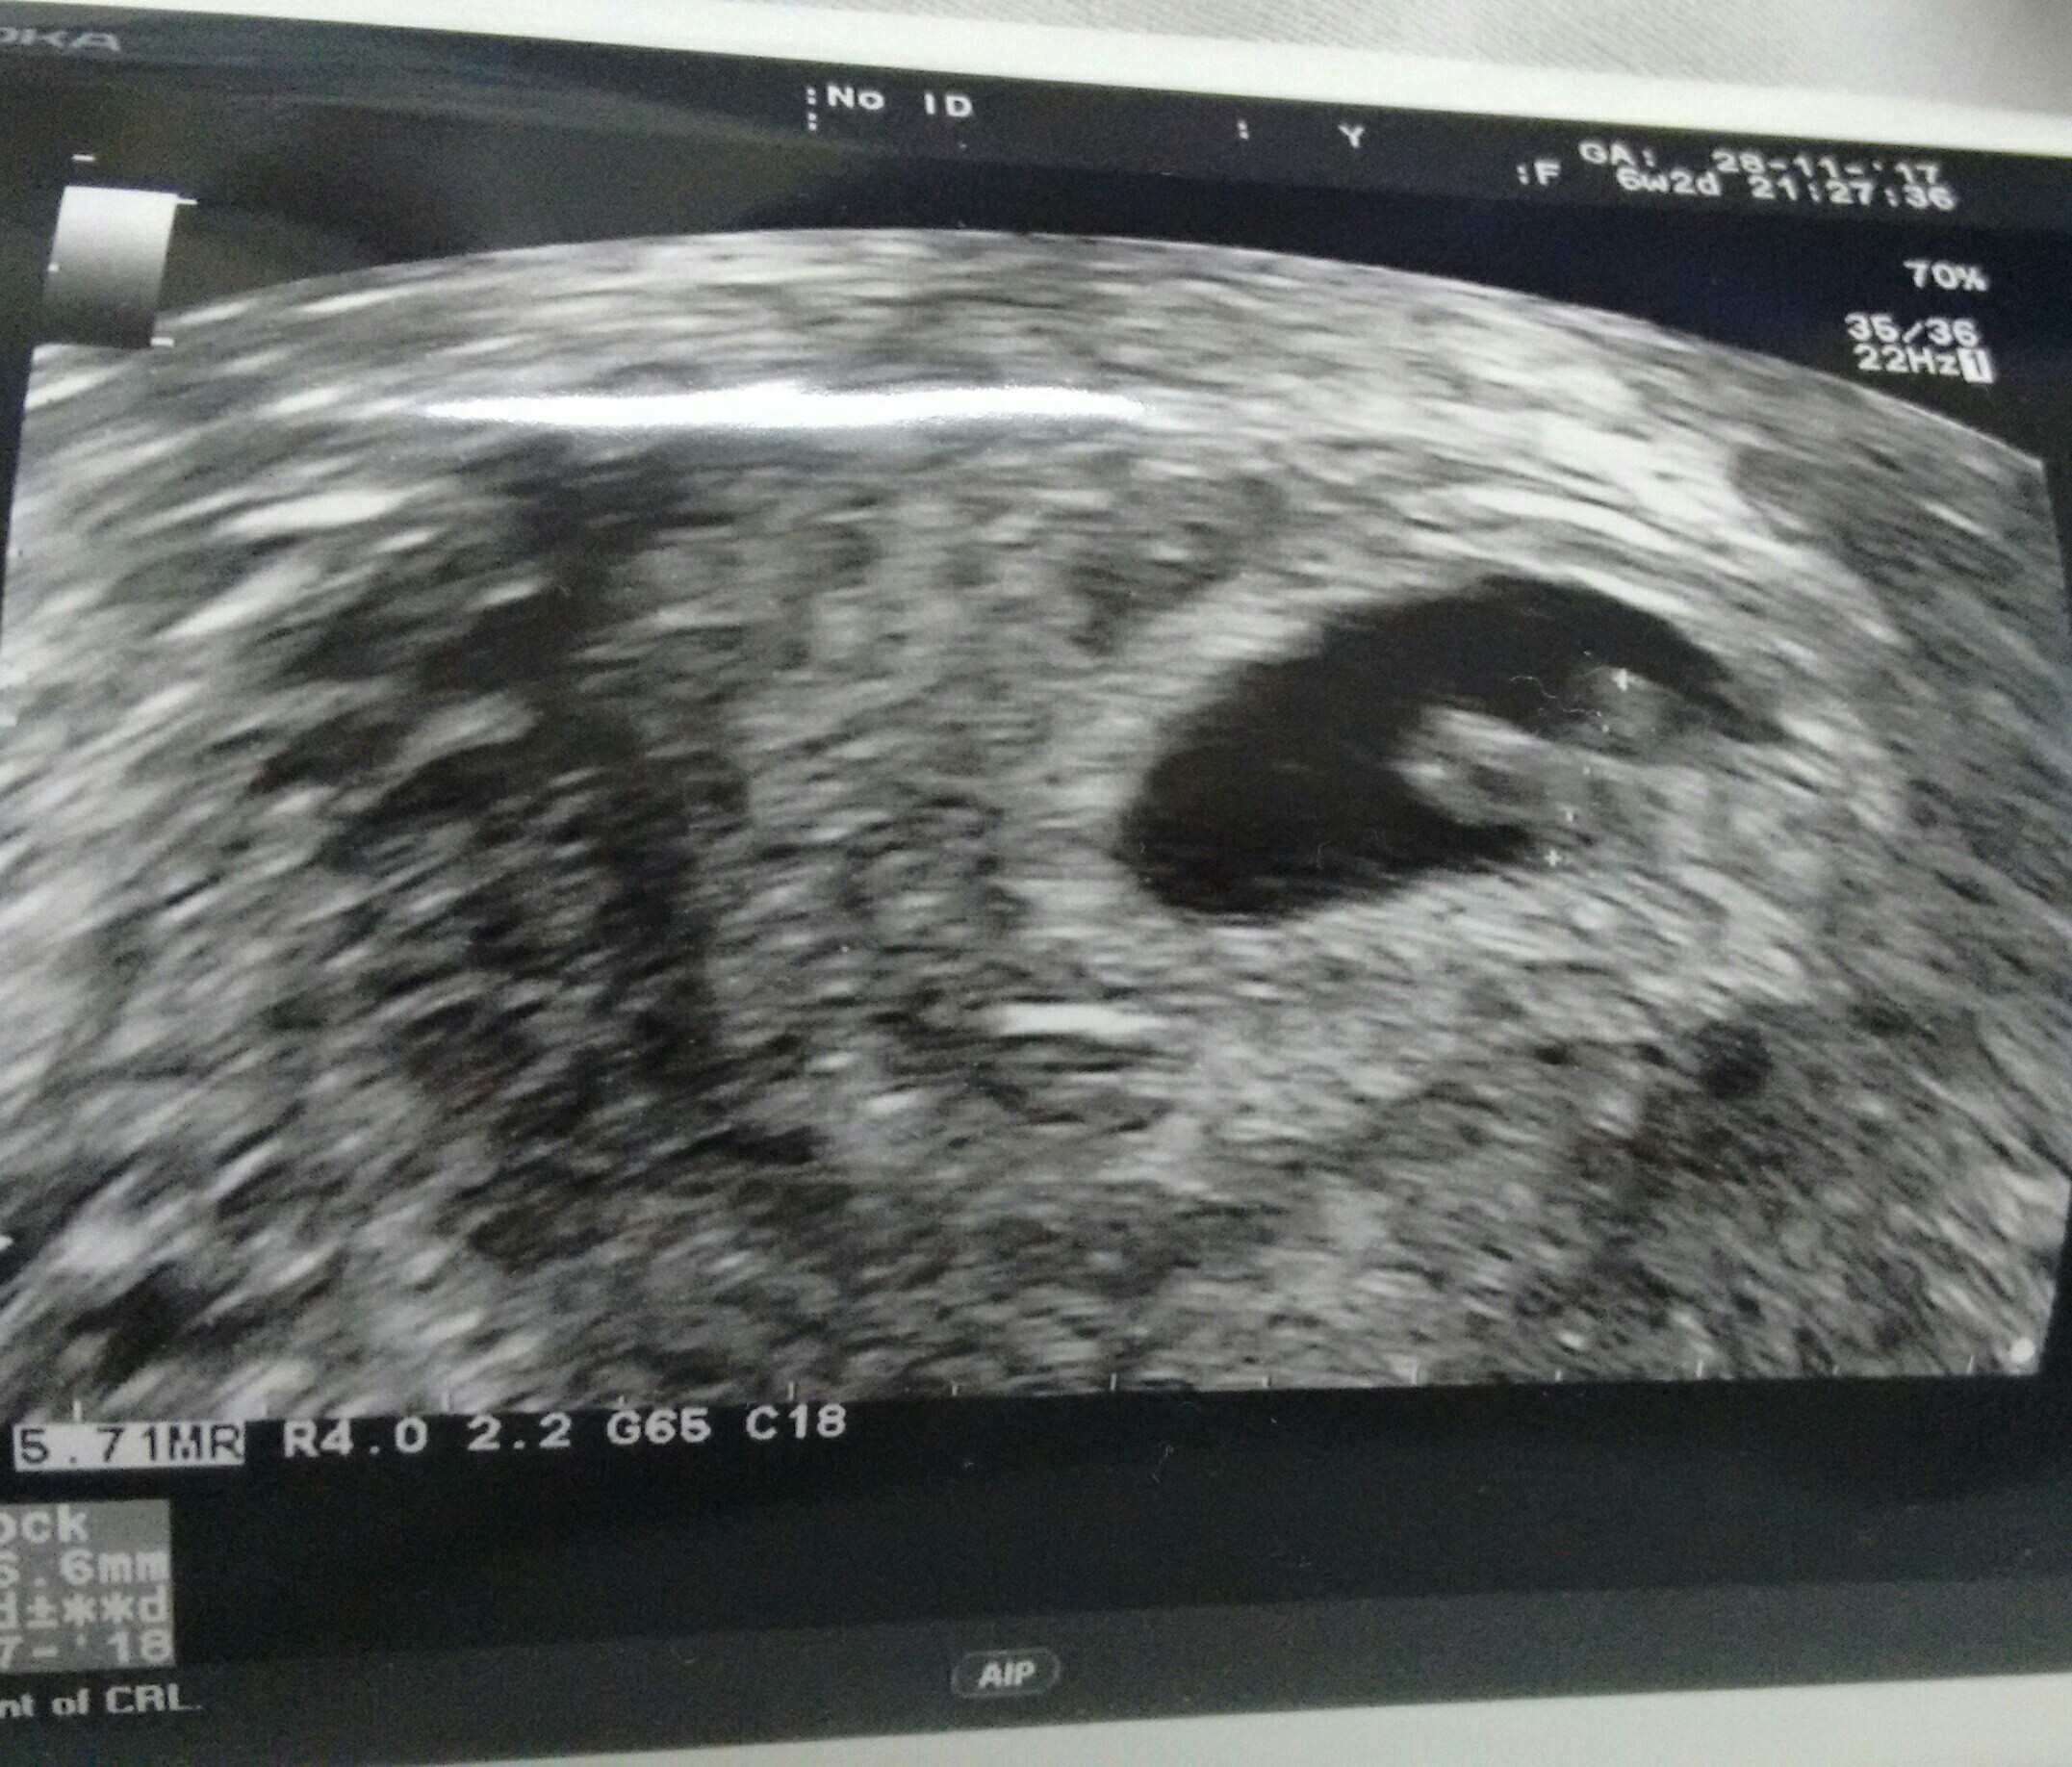

Jestem po badaniu. Dali mi leki i leżę. Dobrze że jest na sali tv i dostęp do internetu.

A powyżej moja fasolka.

Z usg widać 6t2d chyba ;pSliczna fasolka [emoji5] Ktory to tydzien?

Haha, nie pomyslalam zeby popatrzec [emoji6]Z usg widać 6t2d chyba ;p